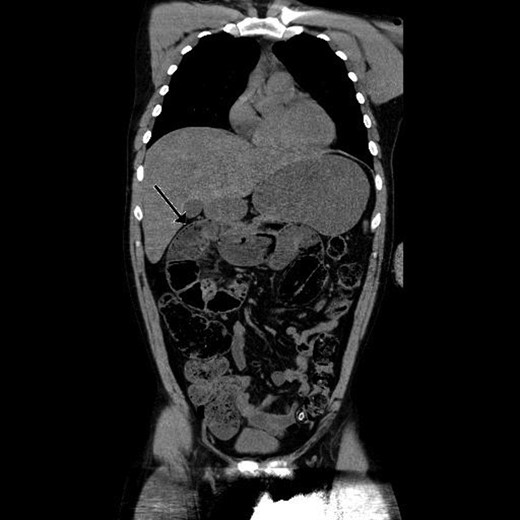

Paraclinical tests showed leucocytosis (10,1 × 109/l) and normal serum lactate. A computed tomography (CT) scan showing gastric retention, encapsulated dilated small intestines in the right upper quadrant with pneumatosis intestinalis and collapsed small intestines distally from this area interpreted as intestinal obstruction (Figs 1 and 2).

Coronal view of preoperative abdominal CT scan demonstrating encapsulated dilated small intestines in the right upper quadrant with pneumatosis intestinalis.